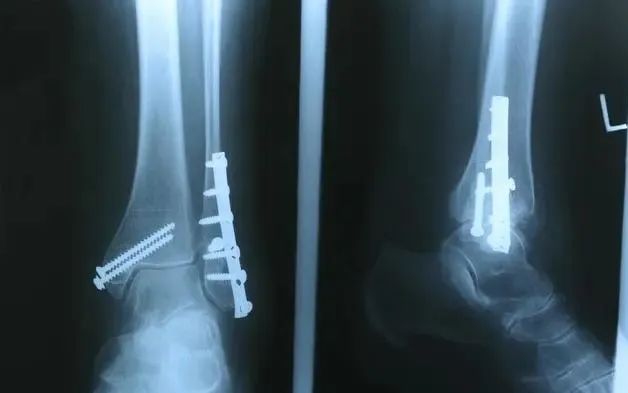

骨折是指在相关因素的影响下,对人体骨骼的完整性和连接性造成破坏,从而引起相关位置的肿胀和疼痛,影响活动和生活。

随着年龄的增长,骨质疏松症逐渐出现,对外界的适应性降低,轻微的外力引起骨折;此外,长期从事某种劳动,或姿势不正确,导致身体某一部位严重劳损,也容易诱发骨折。有些疾病会影响体内钙的吸收,引起骨质疏松,或引起骨质过度破坏,也会引起骨折。常见病有内科疾病.软骨发育不良.骨肿瘤等。骨折后愈合时间的长短,骨折的位置.骨裂的原因.骨折的严重程度与治疗方法密切相关。此外,还有一些个别差异。